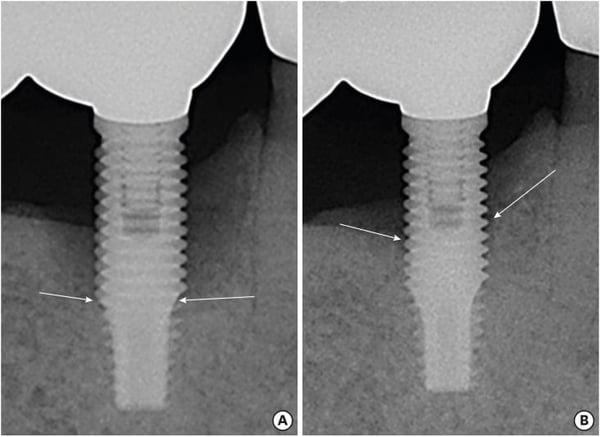

Peri-implantitis still remains one of the most common complications in implant dentistry. It is believed that peri‑implantitis is caused by bacterial‑driven inflammation around dental implants. Therefore, it has been suggested that administration of antibiotics, whether delivered systemically, locally, or via innovative carriers, can help target pathogens